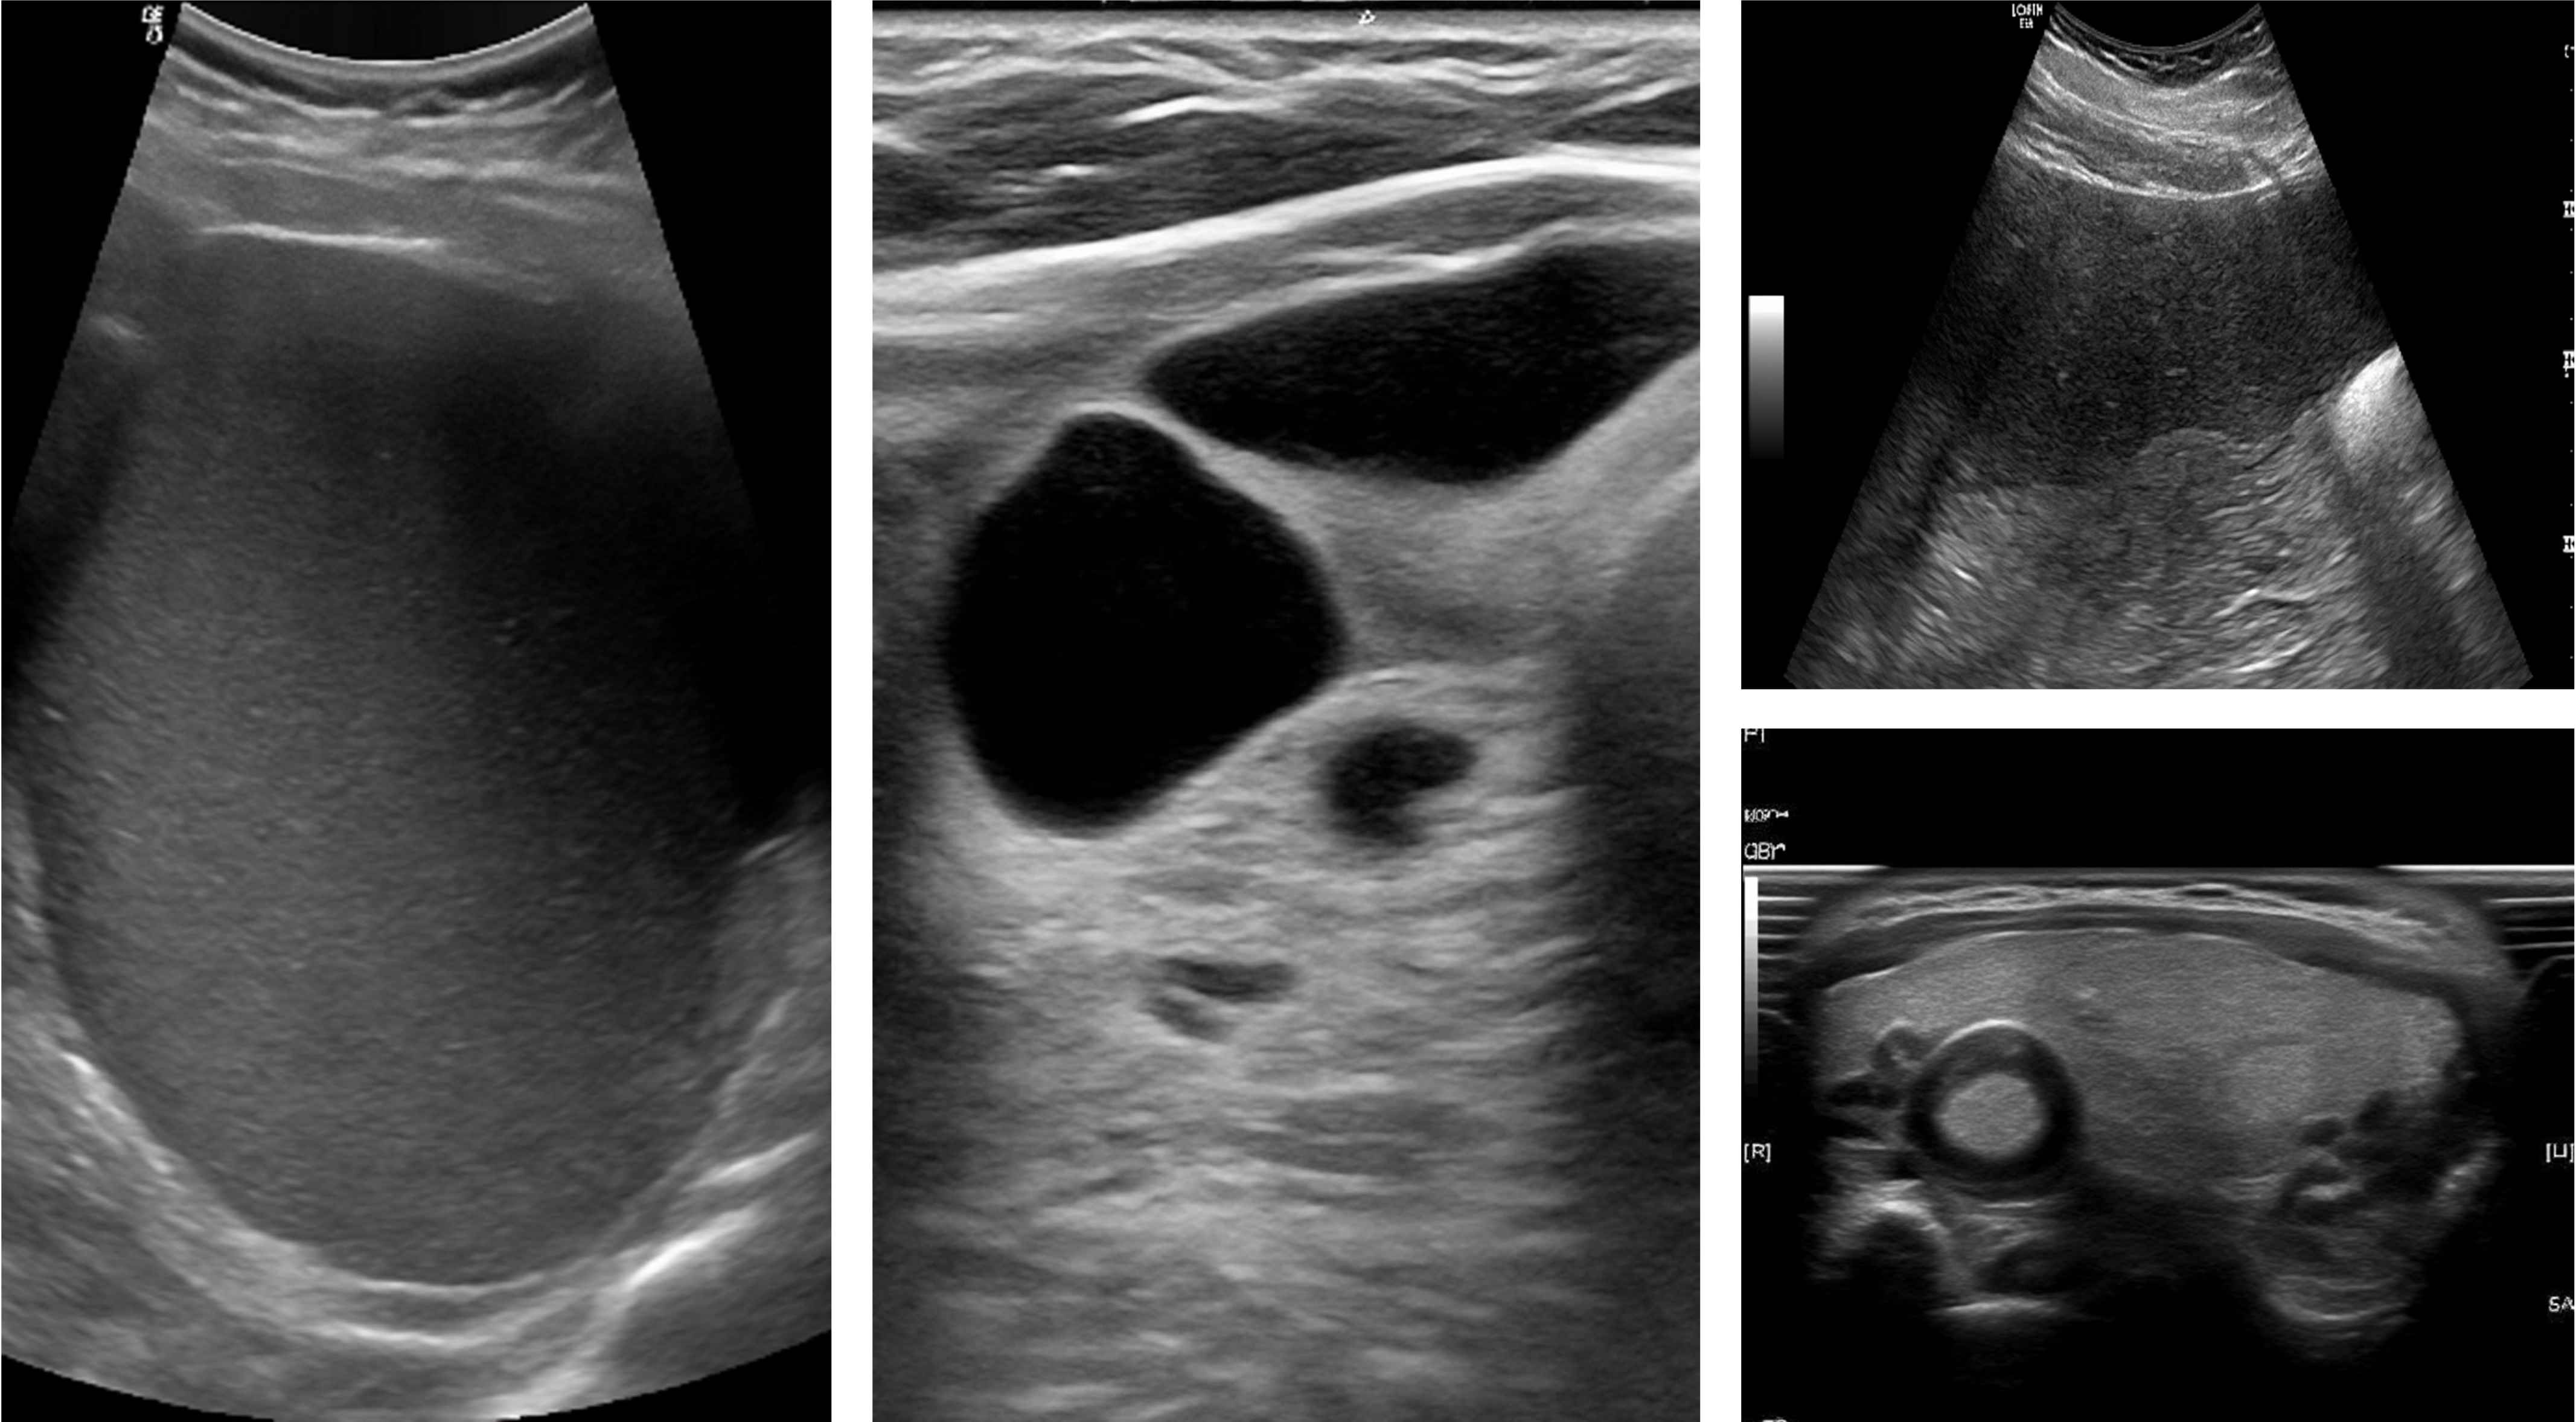

Ultrasound